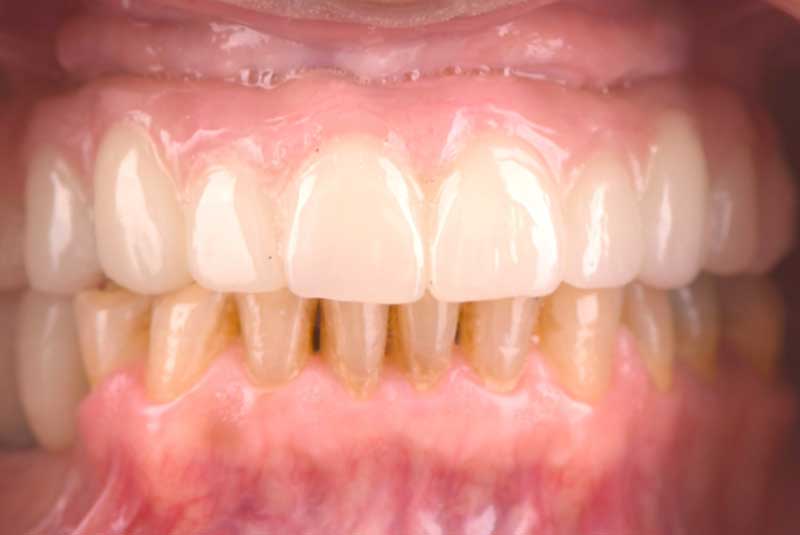

The patient had her implants placed 20 years ago. Four implants, particularly in the maxilla, were not positioned ideally for me to utilize and restore, while the four implants in the mandible were outdated and no longer functional. The patient's primary concern is to restore both function and aesthetics.

All on 6: Facial cut back (PFZ) Zirconia Full arch prosthesis for Maxilla and Mandible Before & After

All on 6 for both arches Implants (#3,4,6,11,13,14,18,21,22,27,28,31)